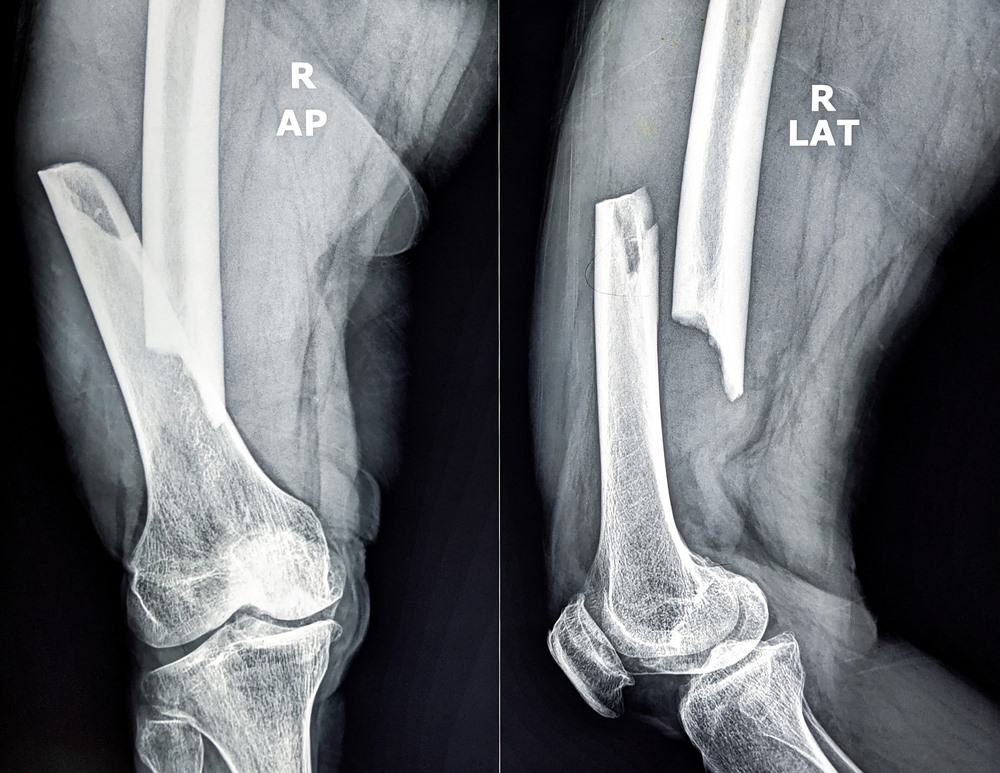

9. Humerusbreuk – Ironisch genoeg helemaal niet grappig

De humerus, oftewel het bovenarmbeen, is een dikke pijp die normaal gesproken wel tegen een stootje kan. Maar als hij breekt, is de pijn absoluut niet grappig. Vooral een ‘spiraalbreuk’, waarbij het bot in een draai breekt, is berucht. Omdat je arm constant in beweging is – zelfs als je gewoon loopt – blijft de pijn wekenlang aanwezig. En als je zenuwen beschadigd raken, kun je tijdelijk of blijvend krachtverlies in je hand en vingers ervaren.